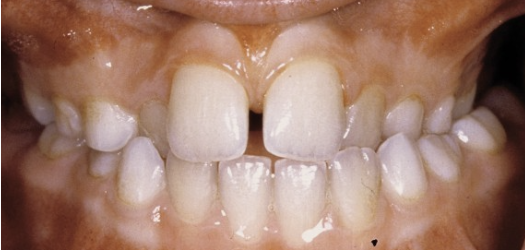

Wat is de klasse II-1 afwijking?

Hier spreken we van een overbeet. De voortanden in de bovenkaak staan dan meestal ook wat verder naar voren. Dit heet ook wel overjet.